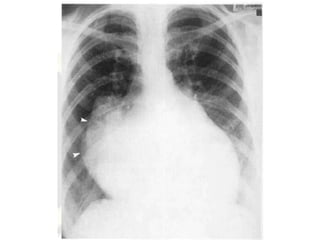

Radiography

• left atrial enlargement

• Extreme left atrial enlargement rarely occurs in isolated

MS - when present, MR is usually severe

• fluoroscopy is required to detect valvular calcification.

• Radiologic changes in the lung fields indirectly reflect

the severity of MS.

• Interstitial edema, an indication of severe obstruction, is manifested as

Kerley B lines (dense, short, horizontal lines most commonly seen in the

costophrenic angles).

• This finding is present in 30% of patients with resting pulmonary arterial

wedge pressures less than 20 mm Hg and in 70% of patients with pressures

greater than 20 mm Hg.

• Severe long-standing mitral obstruction often results in Kerley A lines

(straight, dense lines up to 4 cm in length, running toward the hilum), as

• Kerley B lines

• subpleural

perpendicular lines

1-3 cm in length

• #69 Mitral stenosis with a normal size heart. In the early years of this chronic disease there is often a normal heart size with only subtle signs of left atrial enlargement being evident. The left atrial appendage is prominent and there is pulmonary venous hypertension.

• #71 Left atrial dilatation in mitral stenosis. The grossly enlarged left atrium (arrows) extends beyond the right heart border. Note that the border of the right atrium can be identified where it is joined by the IVC coming up through the diaphragm.